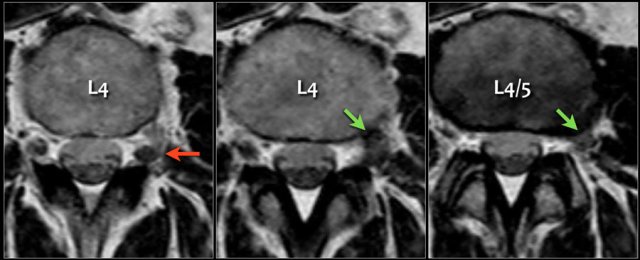

Here another example of disc migration.

Notice how the disc herniation at the L3L4 level migrates caudally behind the body of L4.

Notice that at the L4L5 level the migrated disc simulates a nerve root (green arrow), while in fact the nerve is compressed posteriorly and subsequently moves to the foramen (yellow arrow).